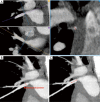

Acquired pulmonary vein stenosis (PVS) is an uncommon occurrence in adults, but one that carries significant morbidity/mortality. PVS can be secondary to neoplastic infiltration/extrinsic compression, non-neoplastic infiltration/extrinsic compression, or iatrogenic intervention. This article: (I) reviews the common causes of acquired PVS; (II) illustrates direct and indirect cross-sectional imaging findings in acquired PVS (in order to avoid misinterpretation of these imaging findings); and (III) details the role of imaging before and after the treatment of acquired PVS.